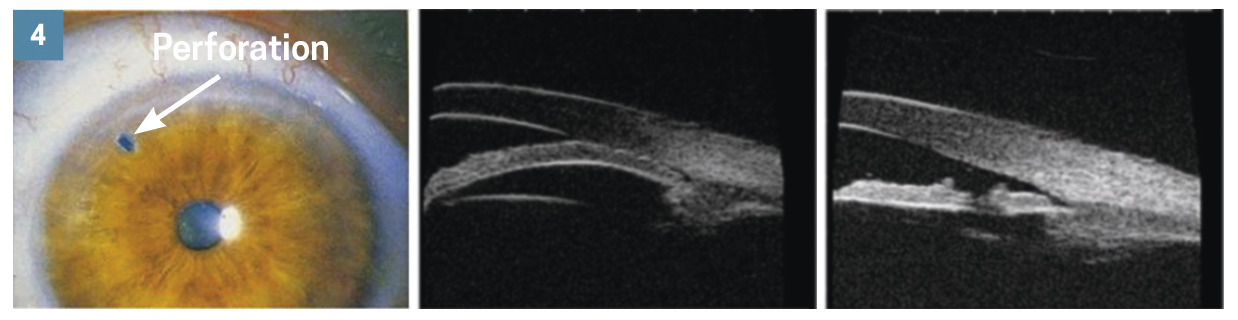

En première intention : lever le blocage pupillaire afin de rouvrir l’angle irido- cornéen, par iridotomie laser (perfo­ration de l’iris au laser : sujet jeune, cristallin transparent ; fig. 4) ou en enlevant le cristallin opacifié par chirurgie de la cataracte chez le sujet âgé (fig. 5). Lorsque la baisse pressionnelle n’est pas suffisante pour empêcher l’évolution de la neuropathie glaucomateuse, la prise en charge complémentaire est très similaire à celle d’un glaucome à angle ouvert : collyres hypotonisants, en monothérapie d’abord puis en combinaison si besoin, et enfin chirurgies filtrantes si le traitement médical n’est pas suffisant.5, 6